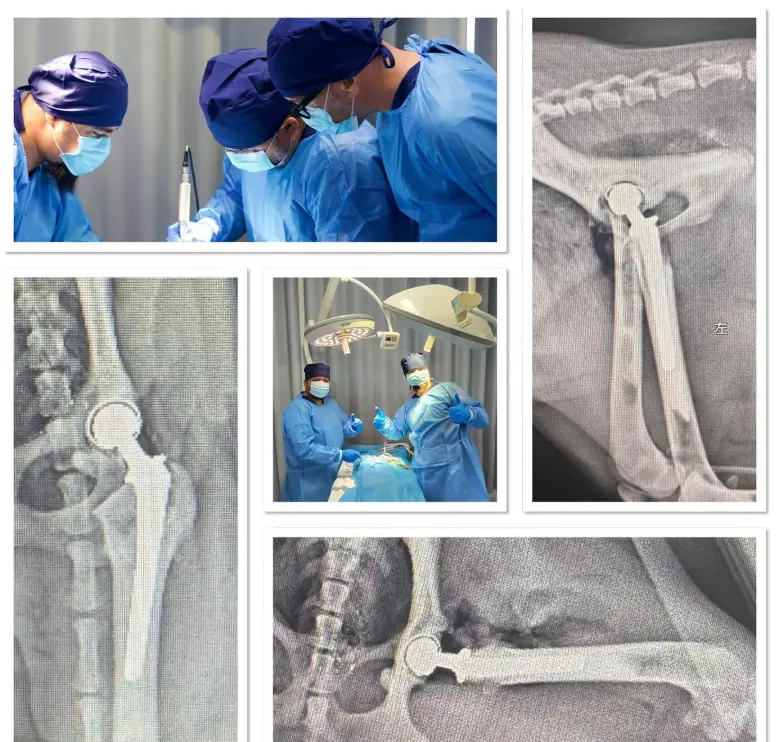

Mayıs 2025 tarihinde katılım sağladığımız BlueSAO 189 Veterinary Orthopedics International Workshop, kliniğimizin cerrahi vizyonunda yeni bir dönemi başlattı. Veteriner ortopedi dünyasının en saygın eğitimlerinden biri olan bu organizasyonda; Total Kalça Protezi (THR), Internal Fiksasyon (Plak/Vida uygulamaları) ve Minimal İnvaziv Cerrahi Teknikleri üzerine yoğun bir teorik ve pratik eğitim süreci tamamladık. Ancak biz biliyoruz ki; modern tıpta cerrahın yeteneği, kullandığı teknolojinin gücüyle sınırlıdır. Karmaşık bir kırık operasyonu veya hassas bir protez yerleşimi, "tahminlere" yer bırakmayacak kadar ciddi bir süreçtir. Bu nedenle, uluslararası arenada edindiğimiz bu ileri cerrahi yetkinlikleri, kliniğimiz bünyesine kattığımız yüksek teknolojili tanı ve laboratuvar altyapısı ile birleştirerek, bölgedeki en kapsamlı tedavi merkezini oluşturduk.

Ortopedik vakalarda ve travmatik yaralanmalarda, standart röntgen görüntüleri bazen yetersiz kalabilir. İki boyutlu görüntülerde kemiklerin üst üste binmesi (süperpozisyon), mikro çatlakların veya eklem içi hasarların gözden kaçmasına neden olabilir.

Kliniğimizde bulunan Bilgisayarlı Tomografi (CT) cihazımız ile:

Acil travma vakalarında zamanla yarışıyoruz. Kliniğimizin Dijital Röntgen Sistemi, saniyeler içinde yüksek kontrastlı ve detaylı görüntüler sunarak hızlı karar vermemizi sağlar.

Başarılı bir ortopedik cerrahi, sadece kemiği onarmak değildir; hastanın genel sisteminin bu operasyonu kaldırıp kaldıramayacağını bilmektir. Pek çok klinik, viral veya bakteriyel analizler için dış laboratuvarlara bağımlıyken, biz bu süreci kendi bünyemizde çözüyoruz.

BlueSAO eğitimiyle kazandığımız global cerrahi vizyonu; Tomografi, Dijital Röntgen ve PCR teknolojilerimizle destekleyerek, minik dostlarımız için maksimum güvenlik ve konfor sağlıyoruz. Kliniğimizde şansa yer yok; bilim, teknoloji ve uzmanlık var.